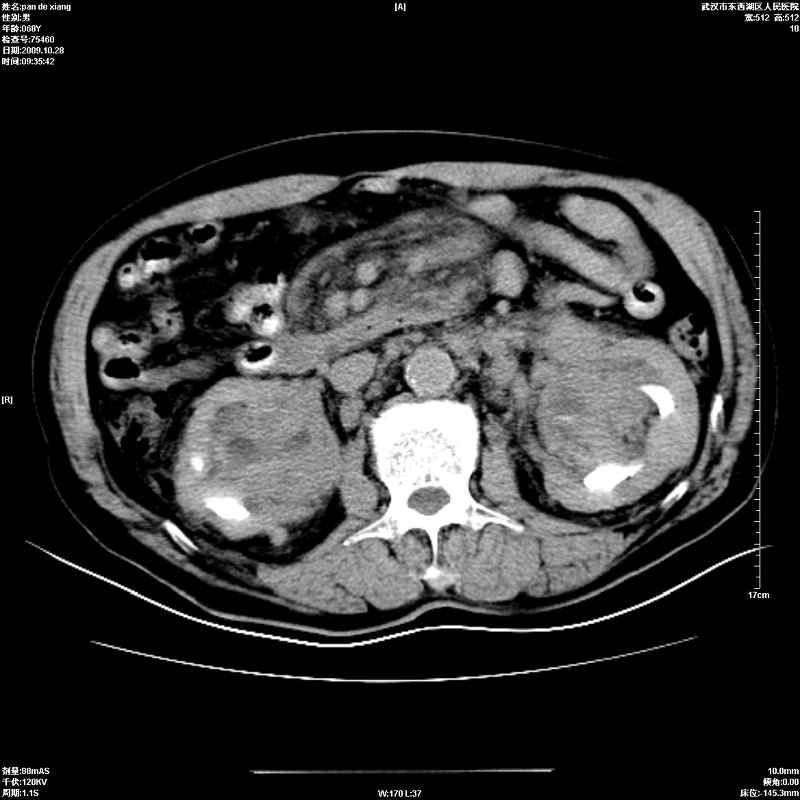

以下是引用杀毒软件在2009-10-28 20:41:00的发言:[br]结合临床考虑---白血病双肾改变或淋巴瘤。

以下是引用zxl51642在2009-10-29 9:59:00的发言:[br]结合临床“单克隆免疫球蛋白血症”,考虑双肾为继发损害并肾功能不全(尿中大量igg及少量iga、igm等大分子免疫球蛋白滤出所致继发损害),椎前软组织肿块为髓外造血。与浆细胞瘤有区别,平扫时有战友说的很清楚。